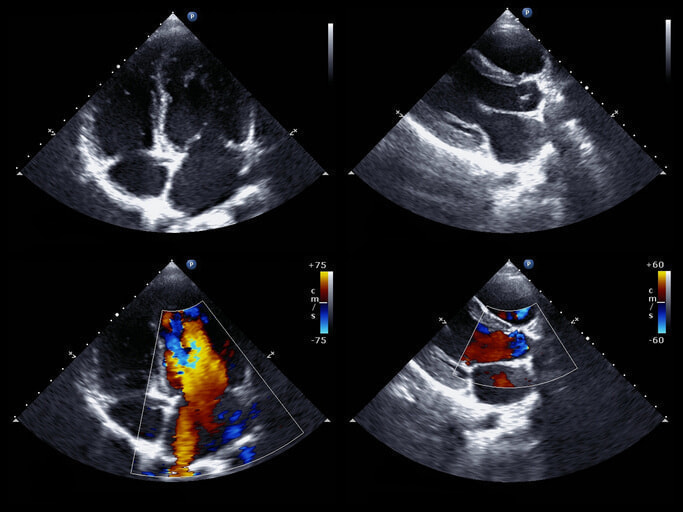

- 心臓超音波検査:心臓の動きや弁膜症の有無などをチェックします。